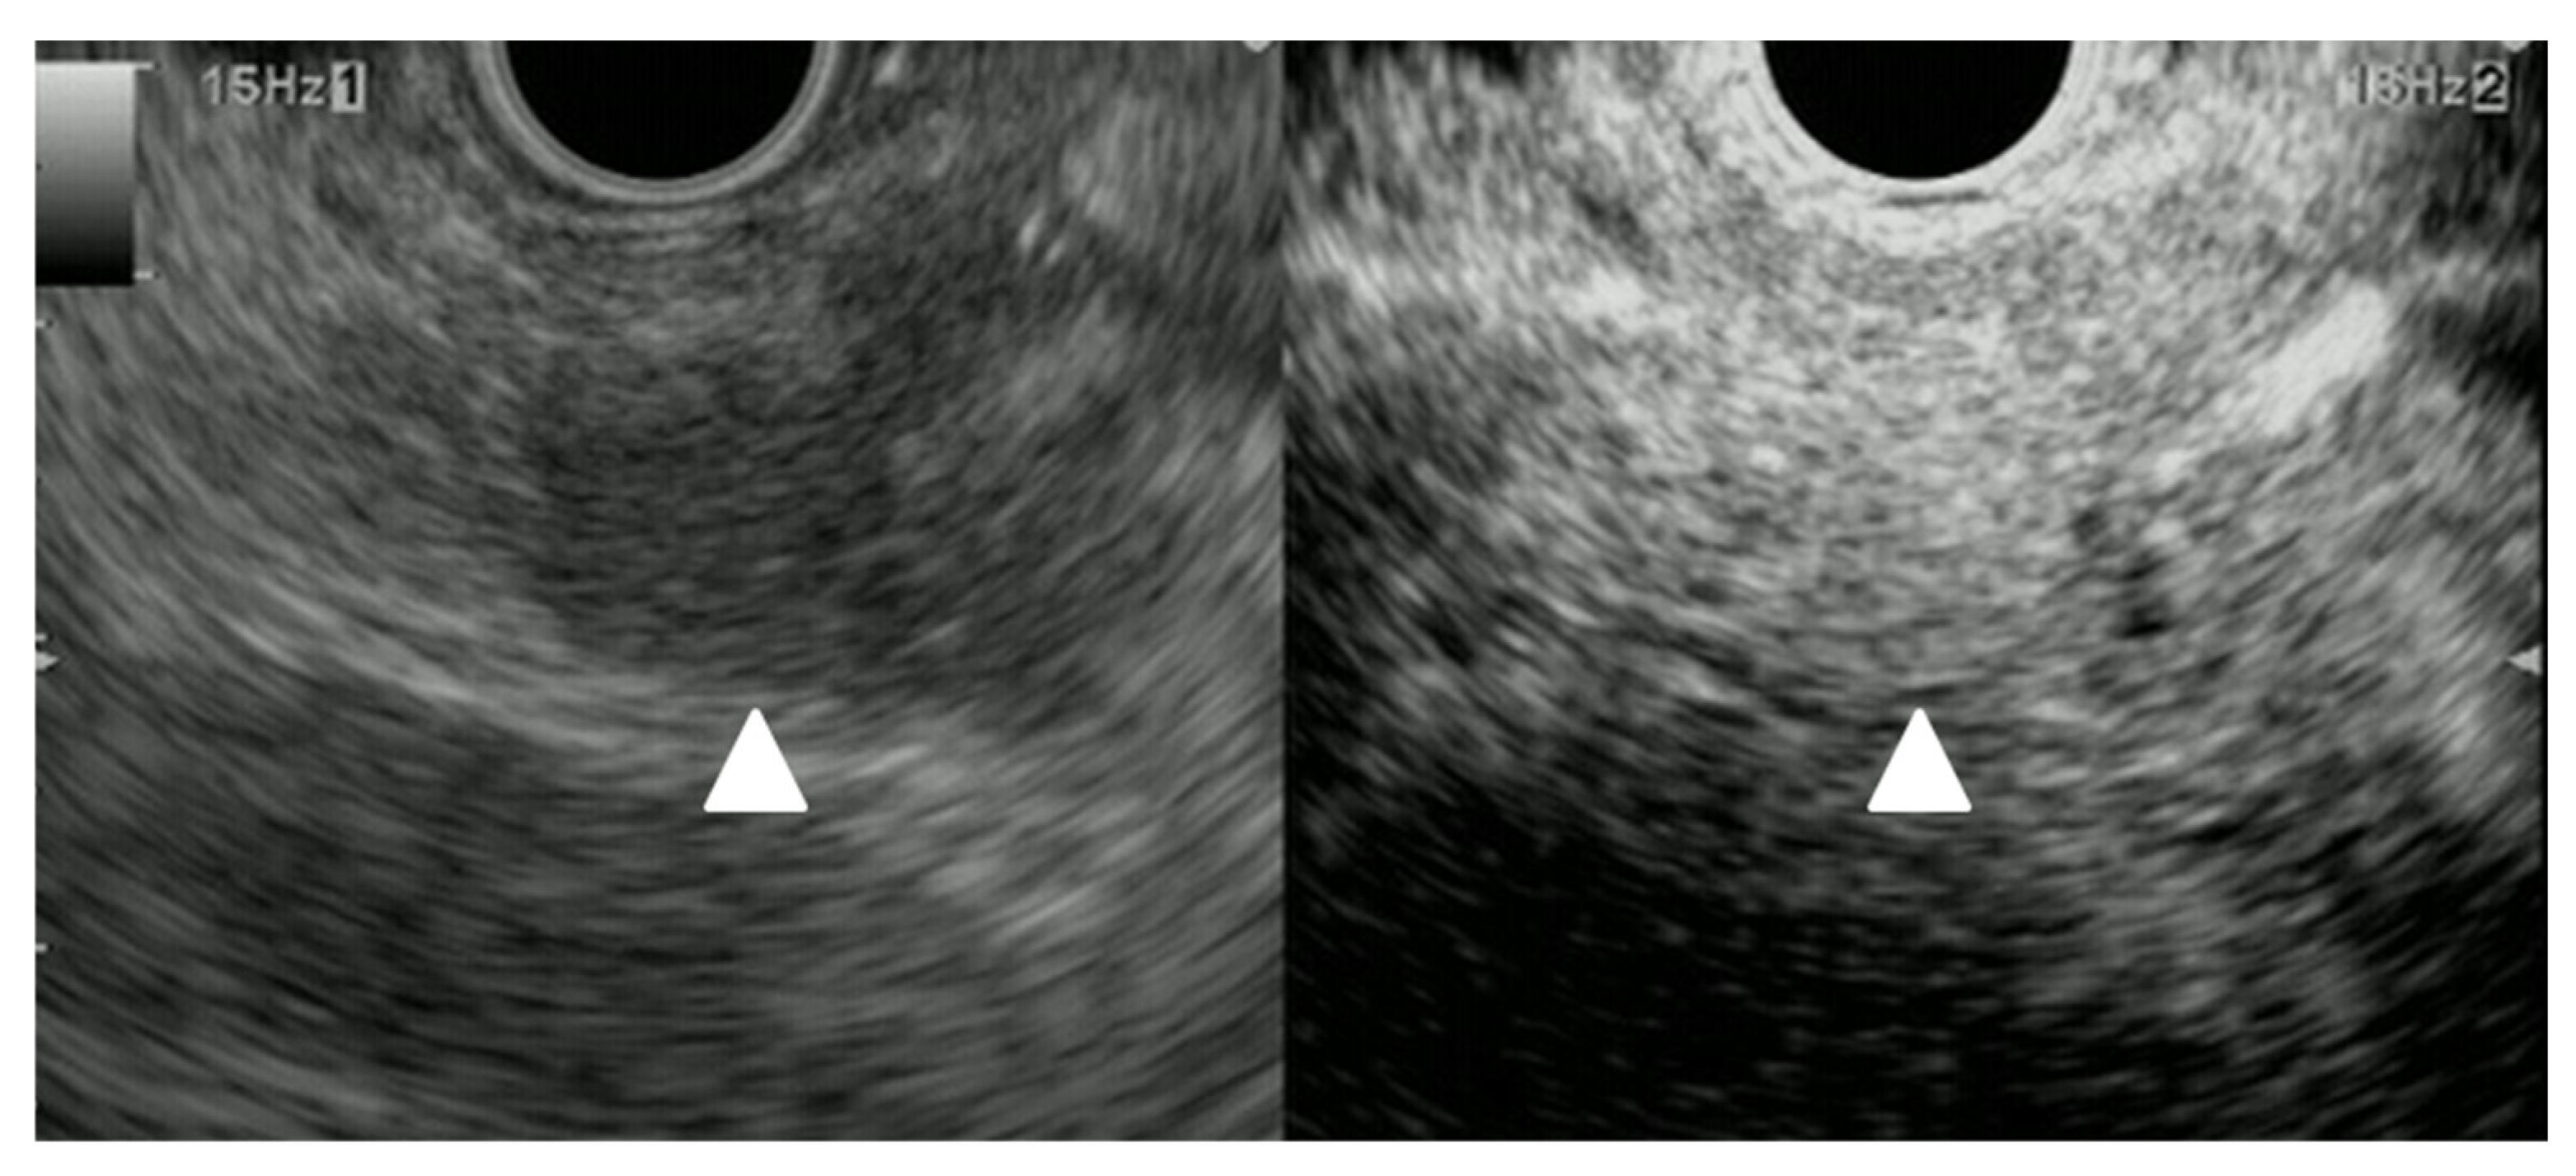

3.3. US and EUS

B-mode US/EUS

| Mostly hypoechoic, homogeneous, or heterogeneous More likely well-defined borders (46%) Anechoic and hyperechoic lesions are possible | Hypoechoic, typically heterogeneous, irregular borders | Hypoechoic, mostly homogeneous, smoothly bordered. Cystic components or cystic solid PanNENs are possible |

| Elastography (small lesions up to 15 mm) [67] | 41% softer or isoelastic, 59% stiffer compared to pancreatic parenchyma | 4% soft or isoelastic, 96% stiffer compared to pancreatic parenchyma | 64% soft or isoelastic, 36% stiffer compared to pancreatic parenchyma |